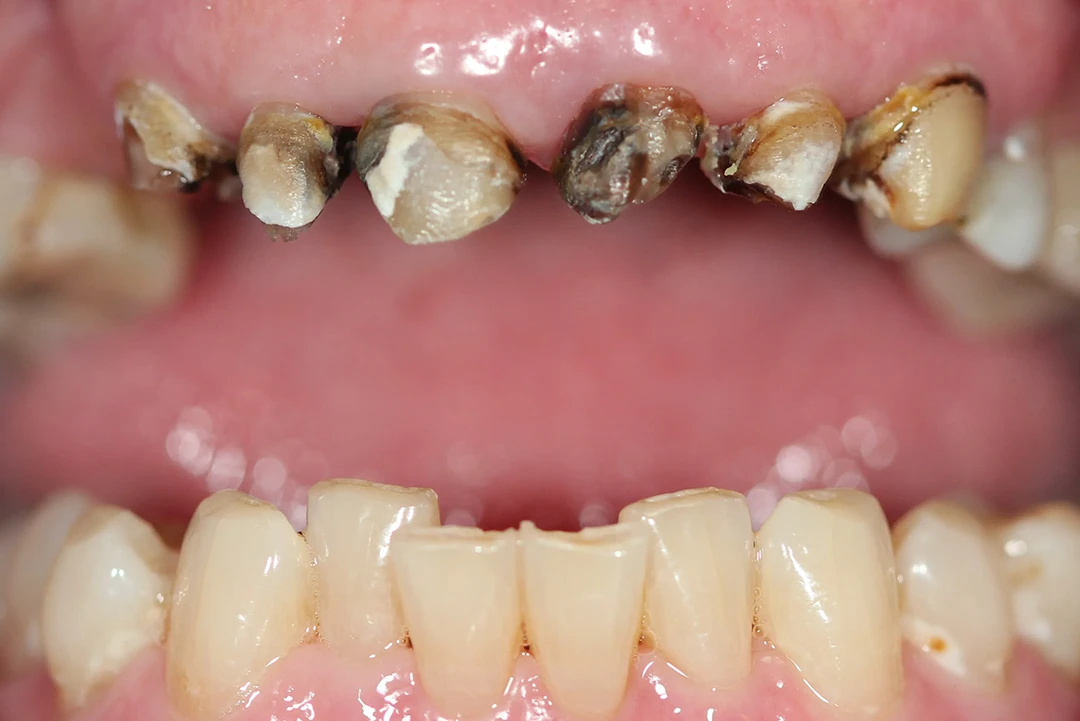

De 61 años nos visita con dientes dañados por caries y una prótesis antigua que ya no podía utilizar. Gracias a la planificación digital y la cirugía guiada, realizamos las extracciones y colocamos implantes con una prótesis fija el mismo día. Recuperó su sonrisa y la confianza de inmediato.